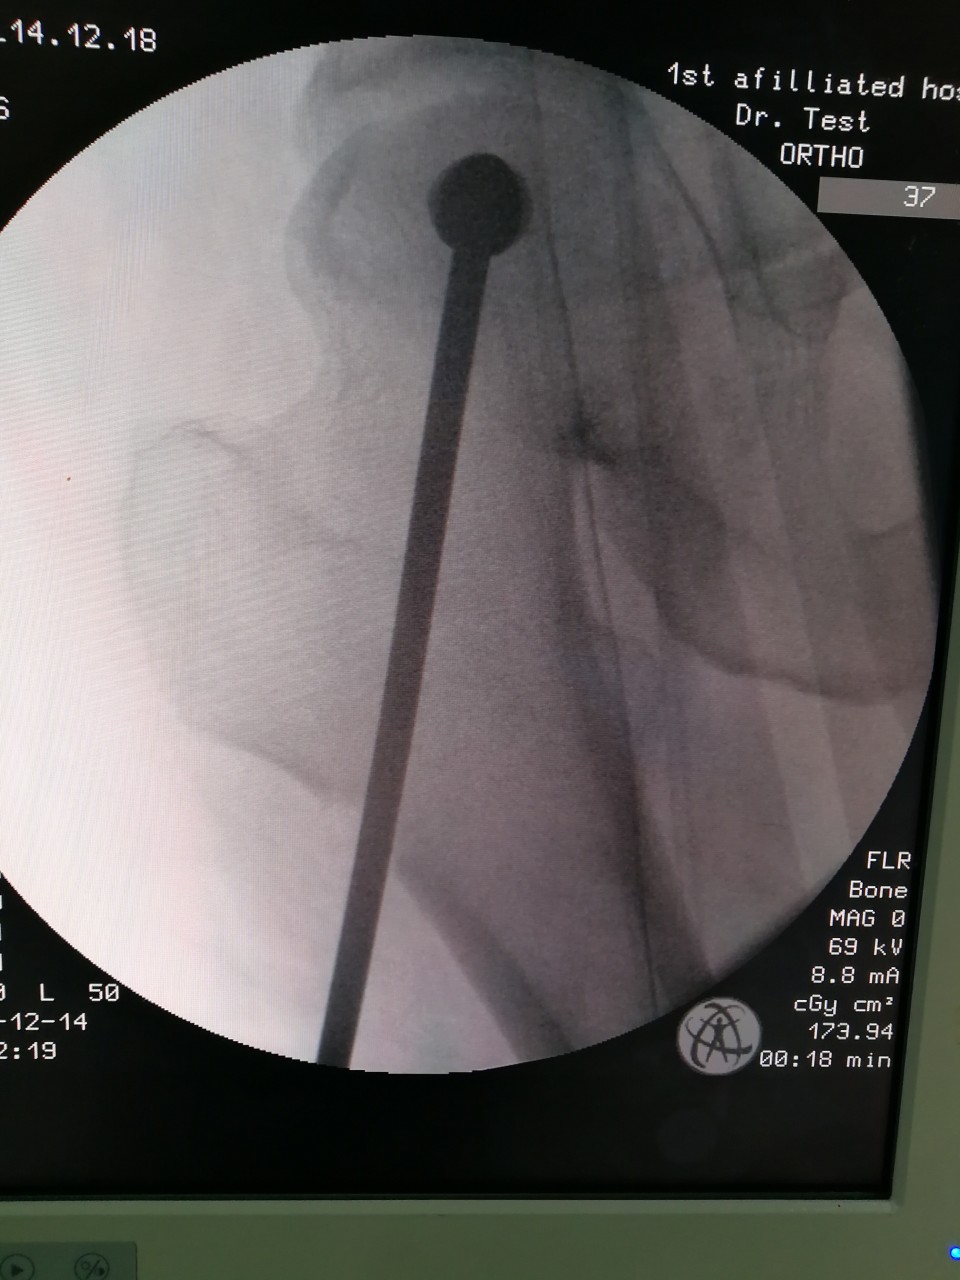

近日,我院创伤骨科病区王刚主任团队利用“天玑”骨科机器人成功为一名股骨头坏死患者施行“机器人导航辅助微创股骨头病灶清除减压+游离腓骨移植术”,患者术后恢复良好,已顺利出院。

股骨头坏死是临床常见疾病之一,常见病因为股骨颈骨折、激素、酗酒等,若早期不进行干预治疗,一旦发生股骨头塌陷,将严重影响行走及日常生活,残疾率高,最终需行髋关节置换术。青壮年早期股骨头坏死的保髋治疗有效率在80%以上,目前国内主流的治疗方法是股骨头病灶清除减压+游离腓骨移植术,但是传统手术手术切口大,病灶定位需要大量射线透视,且不够精确,存在较大局限性。此次创伤骨科王刚主任团队,充分发挥我院“天玑”骨科机器人的优势,利用机器人导航精准定位股骨头坏死中心,再通过小切口进行自体腓骨移植,无需传统内固定辅助,极大地降低了患者费用,减少了术中辐射量。

此项技术,具有微创、精准、术后康复快、经济等显著优势,对于股骨头坏死保髋治疗具有重大意义,同时拓展了骨科机器人的使用范围,使其更好地为患者服务。我院骨科是国家卫计委和工信部批准的全国21家骨科手术机器人牵头运用单位之一,日前我院骨科手术机器人手术量已突破100台。创伤骨科病区将继续充分利用机器人的技术优势在新的领域开展临床治疗,提高省内创伤救治水平,更好地造福患者。